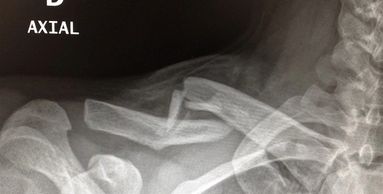

Ocurre con un golpe directo sobre el hombro. Se lesionan los ligamentos que mantienen estables la clavícula al resto del hombro. La cirugía es mínimamente invasiva.

Es la fractura más frecuente alrededor del hombro. Ocurre por un golpe directo sobre el hombro. La cirugía permite una rehabilitación precoz.

Es una fractura frecuente en la población mayor debido a las caídas. También se presenta en pacientes jóvenes debido a accidentes de alta energía.